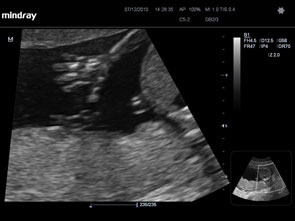

Tashmë shumica e grave shtatzana e kryejnë kontrollin ekografik obstetrikal në javët 18-22 të shtatzënisë. Qëllimi i kontrollit në javën e 18-22 është që të kontrollohet nëse fëmija ka zhvillim normal. Zakonisht, ky quhet kontrolli ekografik i morfologjisë fetale ose kontrolli i anomalive fetale. Thjesht ekografi morfologjike fetale ose ekografia e anomalive.

Ky kontroll kryhet me qëllim që të shihet nëse ka anomali të rritjes dhe zhvillimit strukturor të fëmijës, si spina bifida (shtylla e hapur kurrizore) ose anomali të zemrës dhe për të kontrolluar pozicionin e placentës.

Nëse nuk është kryer ende ndonjë ekografi gjatë kësaj shtatzënie, mjeku obstetër fillimisht do të shohë nëse keni vetëm një fëmijë dhe do t’ju konfirmojë datën kur do të lindni. Ai do të tregojë rrahjet e zemrës dhe pjesë të fëmijës, si fytyra dhe duart, përpara se ta shohë fëmijën me hollësi. Ekografia morfologjike zgjat rreth 15-20 minuta.

Gjatë kësaj ekografie ekzaminohet fetusi nnë mënyrë të detajuar nga lartë poshtë. Organet e brendshme të bebes ekzaminohen nëpërmjet seksioneve tërthore / longitudinale / oblike, të cilat janë të vështira për t’u kuptuar nga pacientja. Në eko, kockat duken të bardha, lëngu i zi dhe indet e buta duken në ngjyrë gri dhe me njolla.